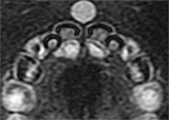

本症例では、当初は先天性唾液腺瘻が上口唇正中に生じたものと診断し、児の成長を待機してからの瘻孔切除を予定していた。しかし初診後6ヵ月に、小孔の裏面に相当する上顎口腔前庭部に小指頭大の弾性軟の腫瘤が出現した(図❷)。MRI検査によってT2強調画像で上口唇正中に境界明瞭で類円形の高信号領域を認め(図❸)、超音波検査では同部には内部にやや不均一な液状の内容物を含む嚢胞状の構造を認めた。病変からは皮膚表面へ向かう管状の構造を認めた(図❹)。

図❸ MR画像(T2強調)。類円形、境界明瞭の高信号領域